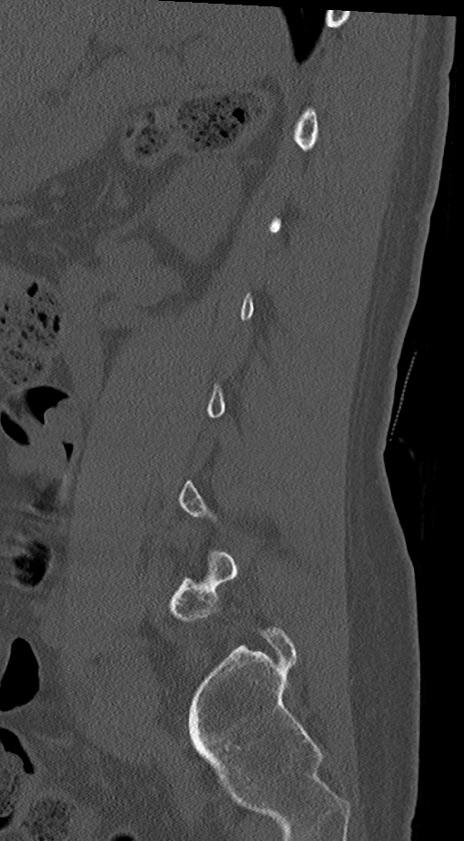

【整形】TIPS症例4 腰椎CT(矢状断像)

腰椎CT

冠状断像